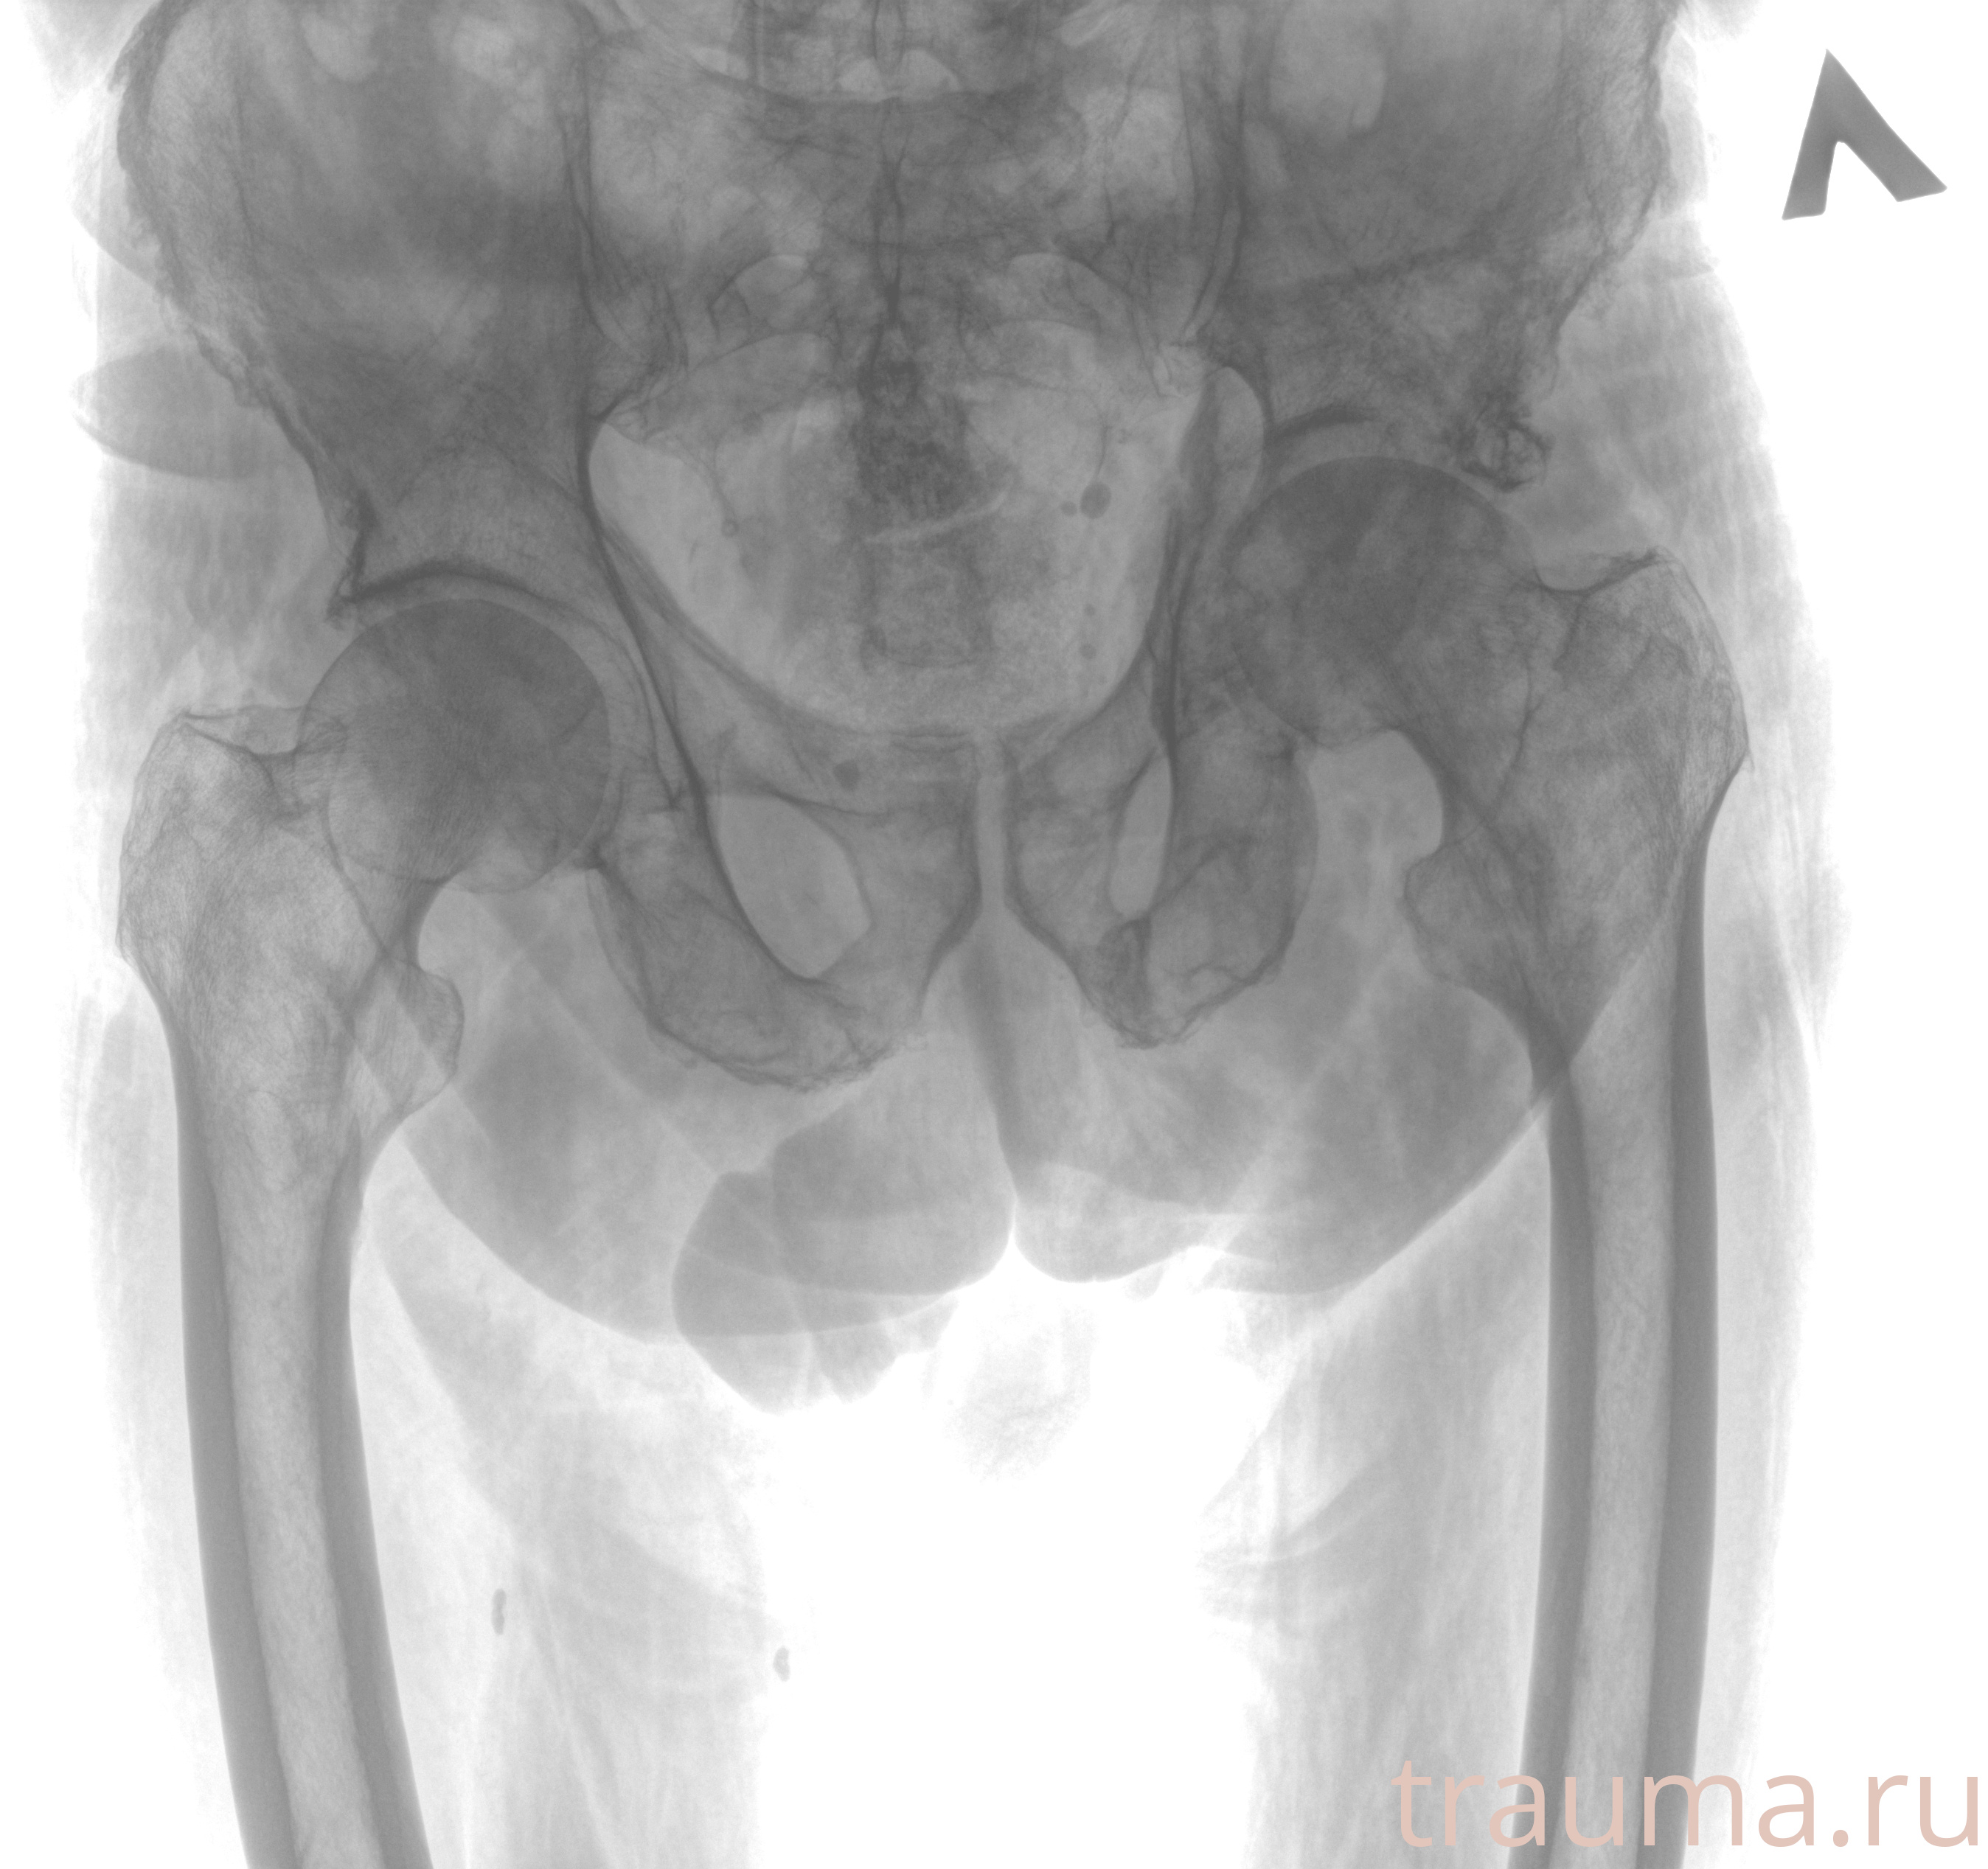

Рентген на дому: по вашему адресу приезжает врач-рентгенолог, травматолог-ортопед с мобильным рентгеновским аппаратом, проводит диагностику травмы или заболевания, делает необходимые рентгенограммы, дает рекомендации по дальнейшему лечению. Получить качественные снимки в домашних условиях возможно благодаря уникальной методике, разработанной МосРентген Центром для института  Склифосовского